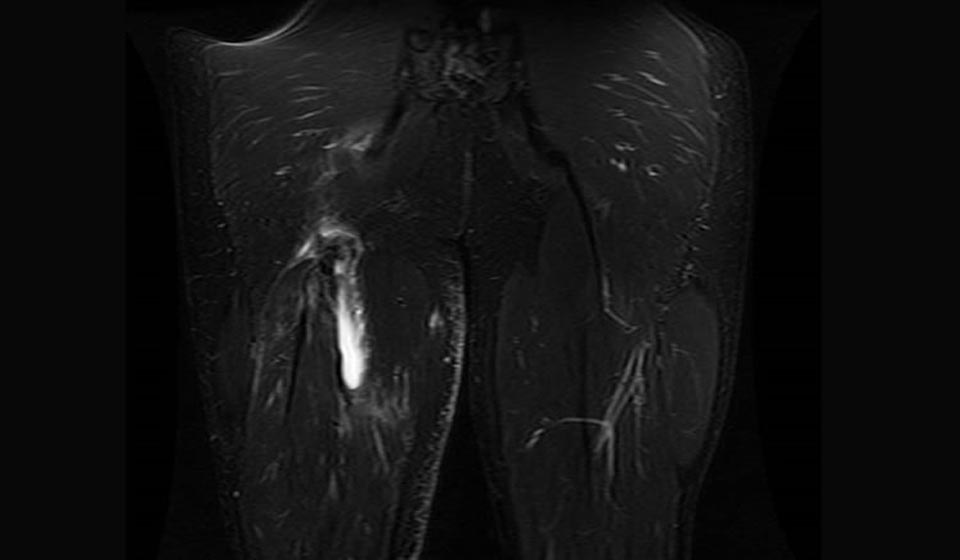

Hamstring muscle injuries — such as a “pulled hamstring” — occur frequently in athletes. They are especially common in athletes who participate in sports that require sprinting, such as track, soccer, and basketball.